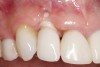

Fig 1. Clinical photograph showing significant issues related to implant midfacial mucosal recession and loss of interdental papillae. This is attributed to incorrect implant positioning (too buccal and too deep); several corrective surgeries resulted in interproximal bone loss, then loss of interdental papillae.

Figure 1